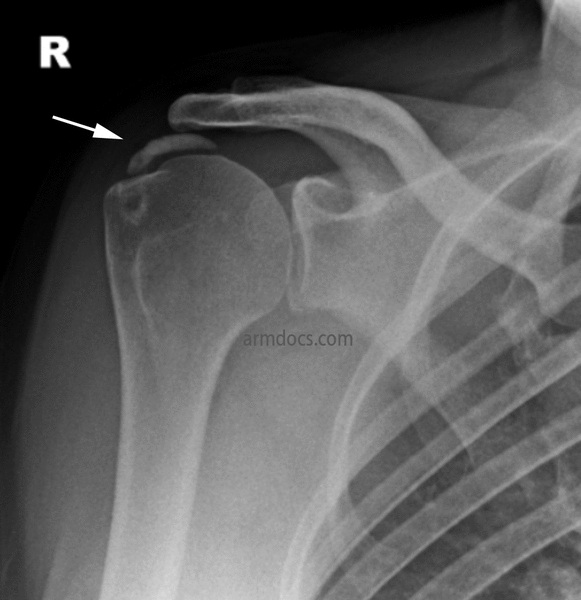

Anteroposterior radiograph of right shoulder showing multiple calcified Calcium Build Up In Shoulder Nhs Your case has been reviewed by an orthopaedic consultant (bone specialist) your painful. Explaining the ongoing management of your injury. If the deposits grow bigger or become irritated, they can cause severe pain. Calcific tendinopathy is caused by a calcium build up in your tendons. Calcific tendonitis is a condition caused by calcium deposits building up in a person’s muscles. Calcium Build Up In Shoulder Nhs.

From www.armdocs.com

Calcific Tendonitis Arm Docs Calcium Build Up In Shoulder Nhs This can cause irritation of the. Explaining the ongoing management of your injury. Calcific tendonitis is a condition caused by calcium deposits building up in a person’s muscles or tendons. Calcific tendonitis is a condition. If calcium builds up in an area, a person may feel pain and discomfort there. If the deposits grow bigger or become irritated, they can. Calcium Build Up In Shoulder Nhs.